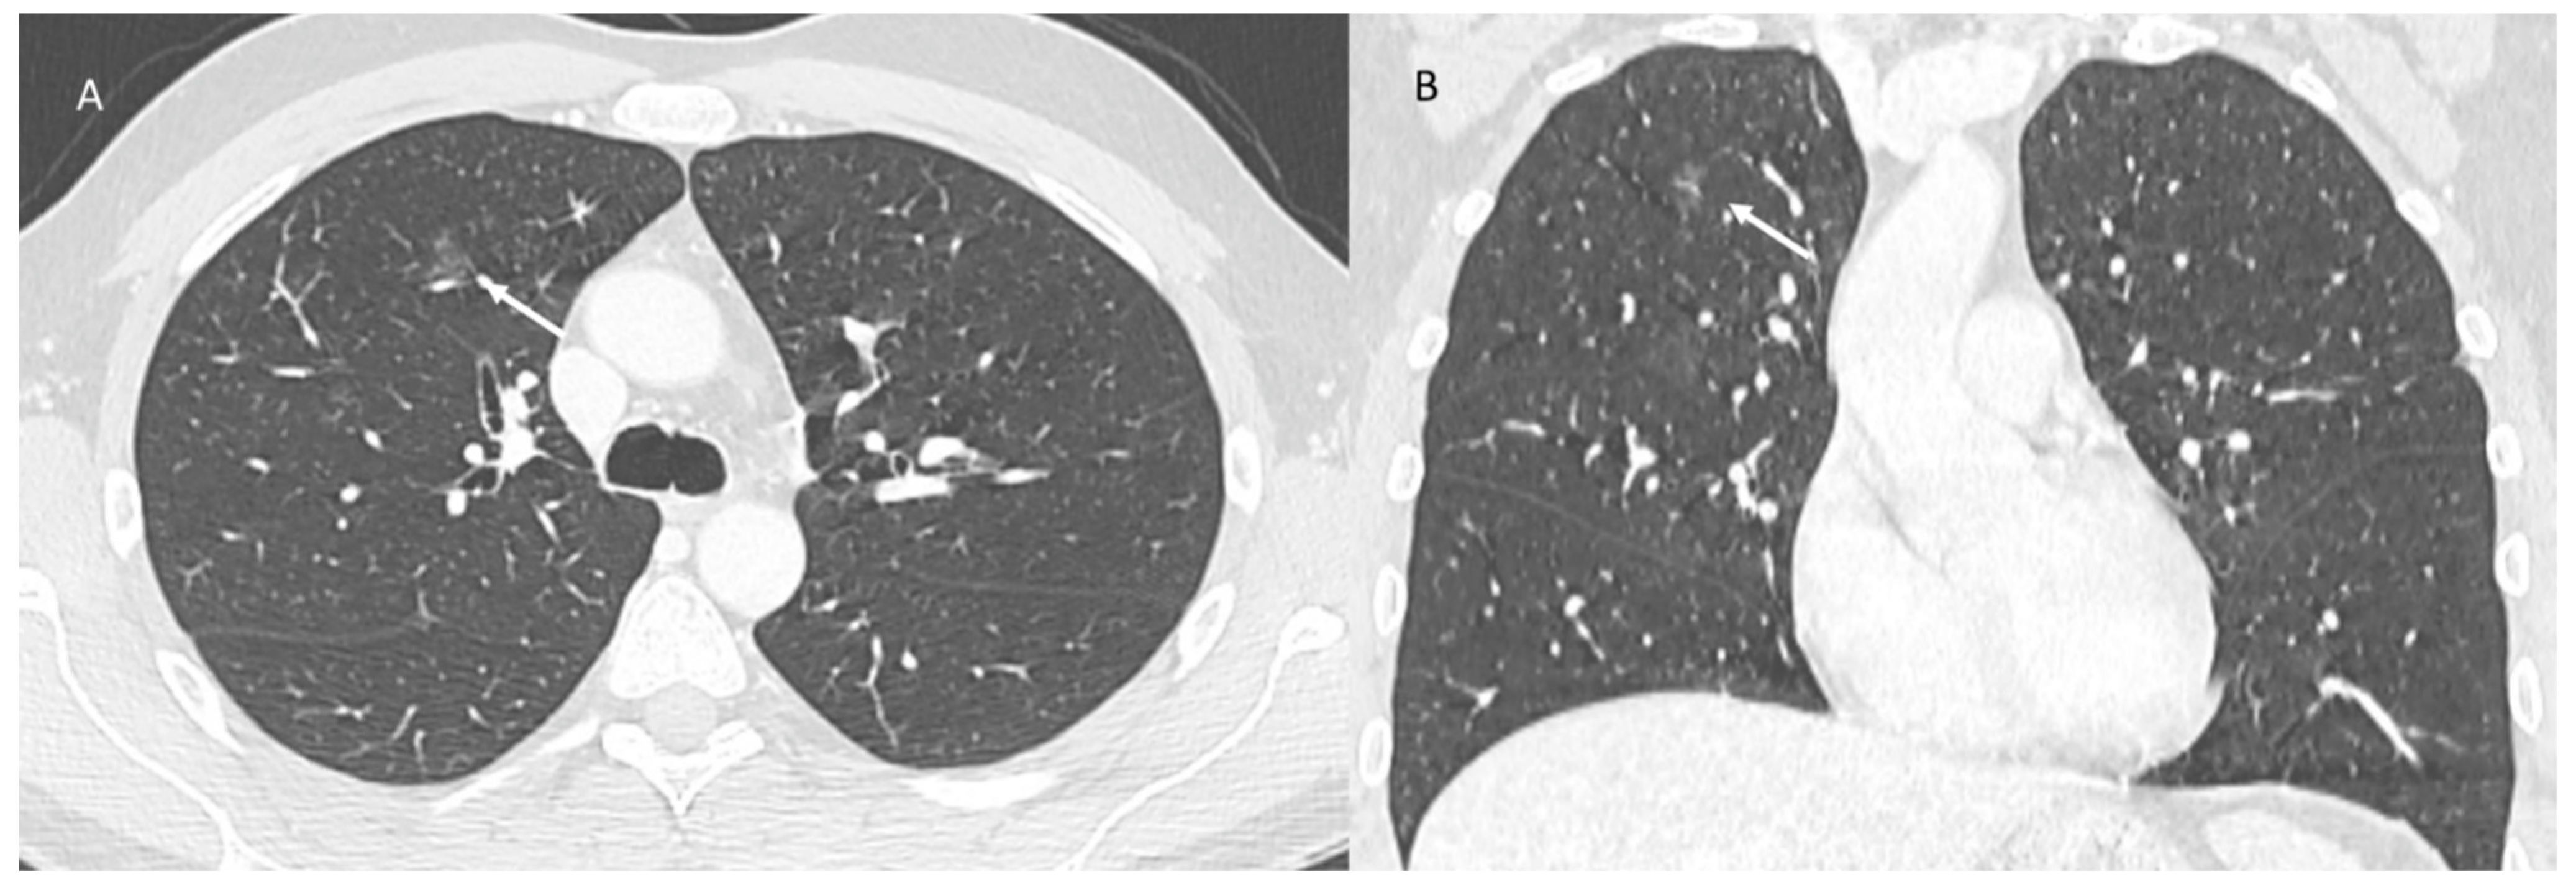

This event has been reported within the lungs [52,118,133], determining radiation recall pneumonitis as acute inflammation within a previously irradiated area. The mechanism of the disease is unclear, but it seems to be related to an immune response. COVID-19 infection is known to cause immunological reactions, such as cytokine storm or multisystem inflammatory syndrome, in children [134,135,136,137]. Just like real infection, the developed vaccines are expected to induce an immune response. The inflammatory state created by the vaccine can favour the development of radiation recall. In fact, the few available papers on the topic suggest that COVID-19 vaccine can cause RRR, considering the time of vaccine administration and this event (Figure 4) [52,133]. The radioactive recall pneumonia model includes consolidated or ground-glass opacities. It should be suspected in all patients with previous radiotherapy with new airspace changes clearly demarcated from the adjacent lung. The main differential diagnosis is infection that does not respect boundaries and occurs outside of the previous radiation field.

Figure 4. Radiation recall pneumonitis (CT scan axial: (A) and coronal: (B)) pattern includes consolidative opacities limited (arrows) to a prior radiation field.